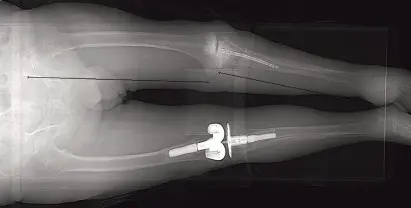

يُعد المسمار النخاعي (Intramedullary Nail) أداة رئيسية في هذا الإجراء. وهو عبارة عن قضيب معدني طويل يتم إدخاله في القناة النخاعية (التجويف المركزي) لكل من عظم الفخذ والقصبة. هذه القناة هي المساحة داخل العظم التي تحتوي عادةً على نخاع العظم. يمتد المسمار عبر الركبة، ويربط العظمين معًا من الداخل، مما يوفر استقرارًا فوريًا ويدعم عملية الاندماج العظمي الطبيعية.

الخطوة 2: إدخال المسمار النخاعي

اختيار المسمار: يُفضل استخدام مسمار نخاعي طويل بزاوية تقوس 5 درجات وزاوية ثني 5 درجات لضمان أفضل محاذاة.

إدخال المسمار: مع وجود سلك التوجيه في مكانه في الفخذ والقصبة، يتم إدخال المسمار في المدور الكبير. يتم دفعه بلطف إلى ديافيسيس الفخذ مع مراقبة فلوروسكوبية. إذا لم يمر المسمار بسهولة، يمكن توسيع قناة الفخذ بـ 1 مم إضافي دون المساس بالتثبيت، حيث سيتم استخدام مسامير تثبيت قريبة.

توجيه المسمار إلى القصبة: بمجرد خروج المسمار من عظم الفخذ القاصي، يتم تثبيت القصبة في الوضع المطلوب، خاصة الوضع الدوراني، حيث يتم دفع المسمار إلى منطقة الميتافيسيس القصبية. يجب التأكد من وضع القصبة تحت الفخذ في كل من الصور الفلوروسكوبية الأمامية والخلفية والجانبية.

يُشدد الأستاذ الدكتور محمد هطيف على أهمية الاهتمام الدقيق بالدوران والزاوية أثناء دخول المسمار إلى القصبة، حيث يصبح الوضع الدوراني ثابتًا بمجرد دخول المسمار إلى ديافيسيس القصبة.

الخطوة 3: تثبيت المسمار

التثبيت القريب: يتم تثبيت المسمار بمسامير قريبة بالقرب من المدور الكبير لضمان ثباته في عظم الفخذ. يجب أن يكون الطرف القريب للمسمار متساويًا مع المدور الكبير لوضع مسمار التثبيت القريب بشكل صحيح.

- الاندماج العظمي (Union): الهدف الأساسي هو تحقيق اندماج عظمي كامل بين الفخذ والقصبة. يُعرف الاندماج شعاعيًا بوجود ترابيق عظمية متصلة تمتد عبر موقع الاندماج. غالبًا ما يُرى هذا لأول مرة في الجانب الخلفي للركبة على الأشعة السينية الجانبية.